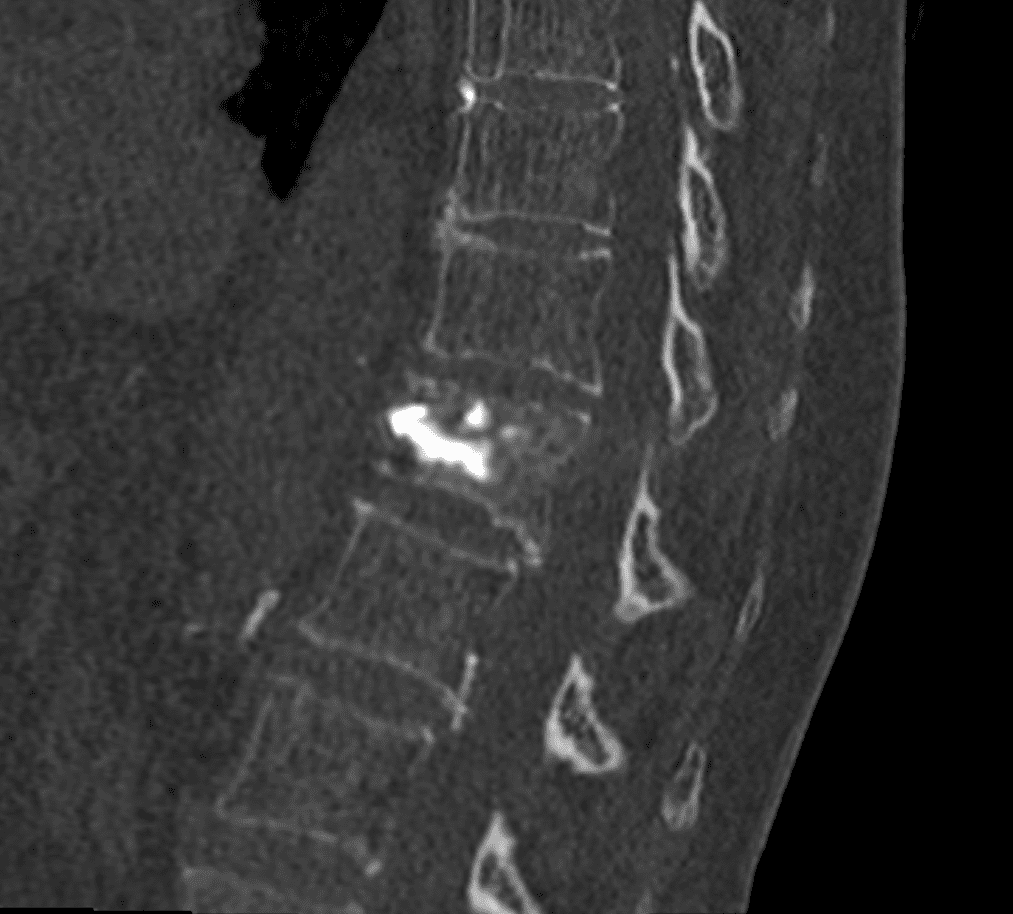

Insertion et déploiement de l’implant

L’implant SPINEJACK est introduit dans le corps vertébral. Une fois en place, il est progressivement déployé pour redresser la vertèbre et restaurer sa hauteur, améliorant ainsi la posture et réduisant la douleur.

Injection du ciment

Pour assurer la stabilité de l’ensemble, du ciment osseux est injecté de manière contrôlée autour de l’implant, garantissant ainsi la consolidation et la pérennité du résultat.